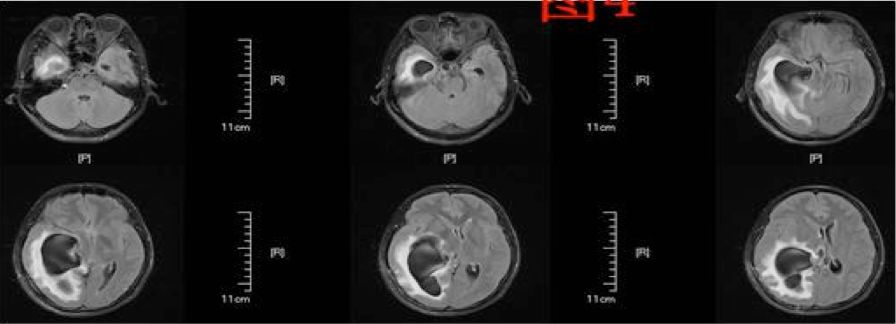

患者于术后第64天再次入院,入院后行头部MRI(图4)检查提示右侧侧脑室颞角、后角扩张并周围脑组织水肿、中线明显移位,并行腰穿测压为280cmH2O,诊断为右侧侧脑室三角区脑膜瘤切除术后孤立颞角综合征,遂于术后第68天行侧脑室颞角腹腔分流术,分流管为美敦力可调压力分流管,术中设定压力范围为105~125mmH2O,术后复查头部CT以及MRI(图5、6)。

图4. 磁共振检查提示右侧侧脑室颞角、后角扩张并周围脑组织水肿、中线明显移位。